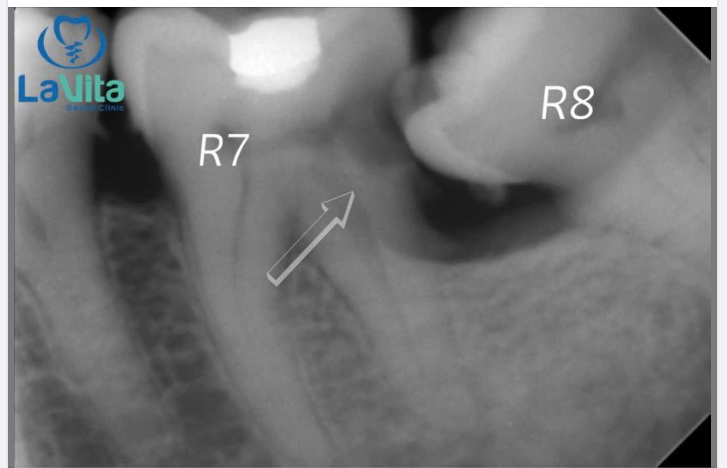

Nhổ răng khôn không đơn thuần là rút chiếc răng ra khỏi xương hàm, mà nó phức tạp hơn, đặc biệt nếu nó bị mọc kẹt.